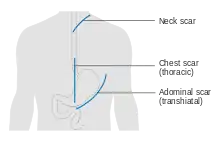

Surgery

Esophagectomy is the removal of a segment of the esophagus; as this shortens the length of the remaining esophagus, some other segment of the digestive tract is pulled up through the chest cavity and interposed. This is usually the stomach or part of the large intestine (colon) or jejunum. Reconnection of the stomach to a shortened esophagus is called an esophagogastric anastomosis.[61]

Esophagectomy can be performed using several methods. The choice of the surgical approach depends on the characteristics and location of the tumor, and the preference of the surgeon. Clear evidence from clinical trials for which approaches give the best outcomes in different circumstances is lacking.[61] A first decision, regarding the point of entry, is between a transhiatial and a transthoracic procedure. The more recent transhiatial approach avoids the need to open the chest; instead the surgeon enters the body through an incision in the lower abdomen and another in the neck. The lower part of the esophagus is freed from the surrounding tissues and cut away as necessary. The stomach is then pushed through the esophageal hiatus (the hole where the esophagus passes through the diaphragm) and is joined to the remaining upper part of the esophagus at the neck.[61]

The traditional transthoracic approach enters the body through the chest, and has a number of variations. The thoracoabdominal approach opens the abdominal and thoracic cavities together, the two-stage Ivor Lewis (also called Lewis–Tanner) approach involves an initial laparotomy and construction of a gastric tube, followed by a right thoracotomy to excise the tumor and create an esophagogastric anastomosis. The three-stage McKeown approach adds a third incision in the neck to complete the cervical anastomosis. Recent approaches by some surgeons use what is called extended esophagectomy, where more surrounding tissue, including lymph nodes, is removed en bloc.[61]